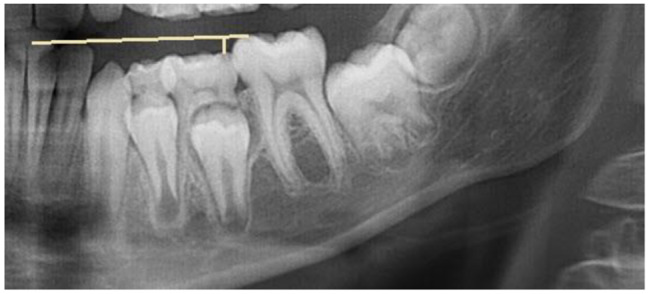

Results: Of 5645 records, 42 papers qualified for the final analysis. The evaluation of infraoccluded deciduous teeth was mainly (n = 37) performed by quantitative and semiquantitative assessment of the extent of infraposition at the occlusal level. The measurement reference differed considerably. Fewer studies have analyzed ankylosed deciduous teeth at the alveolar level by examining the contour of the alveolar ridge (n = 7) or the height of the alveolar process (n = 5). Even fewer studies (n = 4) have performed qualitative analysis at the skeletal level by evaluating the influence of the vertical skeletal growth pattern on the incidence of ankylosed deciduous teeth.

Conclusions: To carry out a comprehensive evaluation of infraoccluded deciduous teeth, an assessment of the occlusal, alveolar and potentially skeletal levels is advisable. Radiographic investigations i.e. panoramic radiographs are therefore essential as a supplement to clinical examination. There is a need for standardization and objectification of the methods for the classification of infraoccluded deciduous teeth to give a general recommendation of clinical performance.